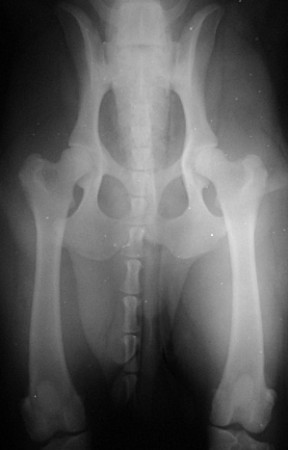

Displasia Coxo-femural

Todos os nossos cães são submetidos a radiografias coxo-femural antes de serem selecionados para o programa de reprodução, afim de controlar a disseminação desta anomalia genética.

Somente o exame radiográfico realizado dentro de normas técnicas adequadas pode confirmar os casos de displasia.